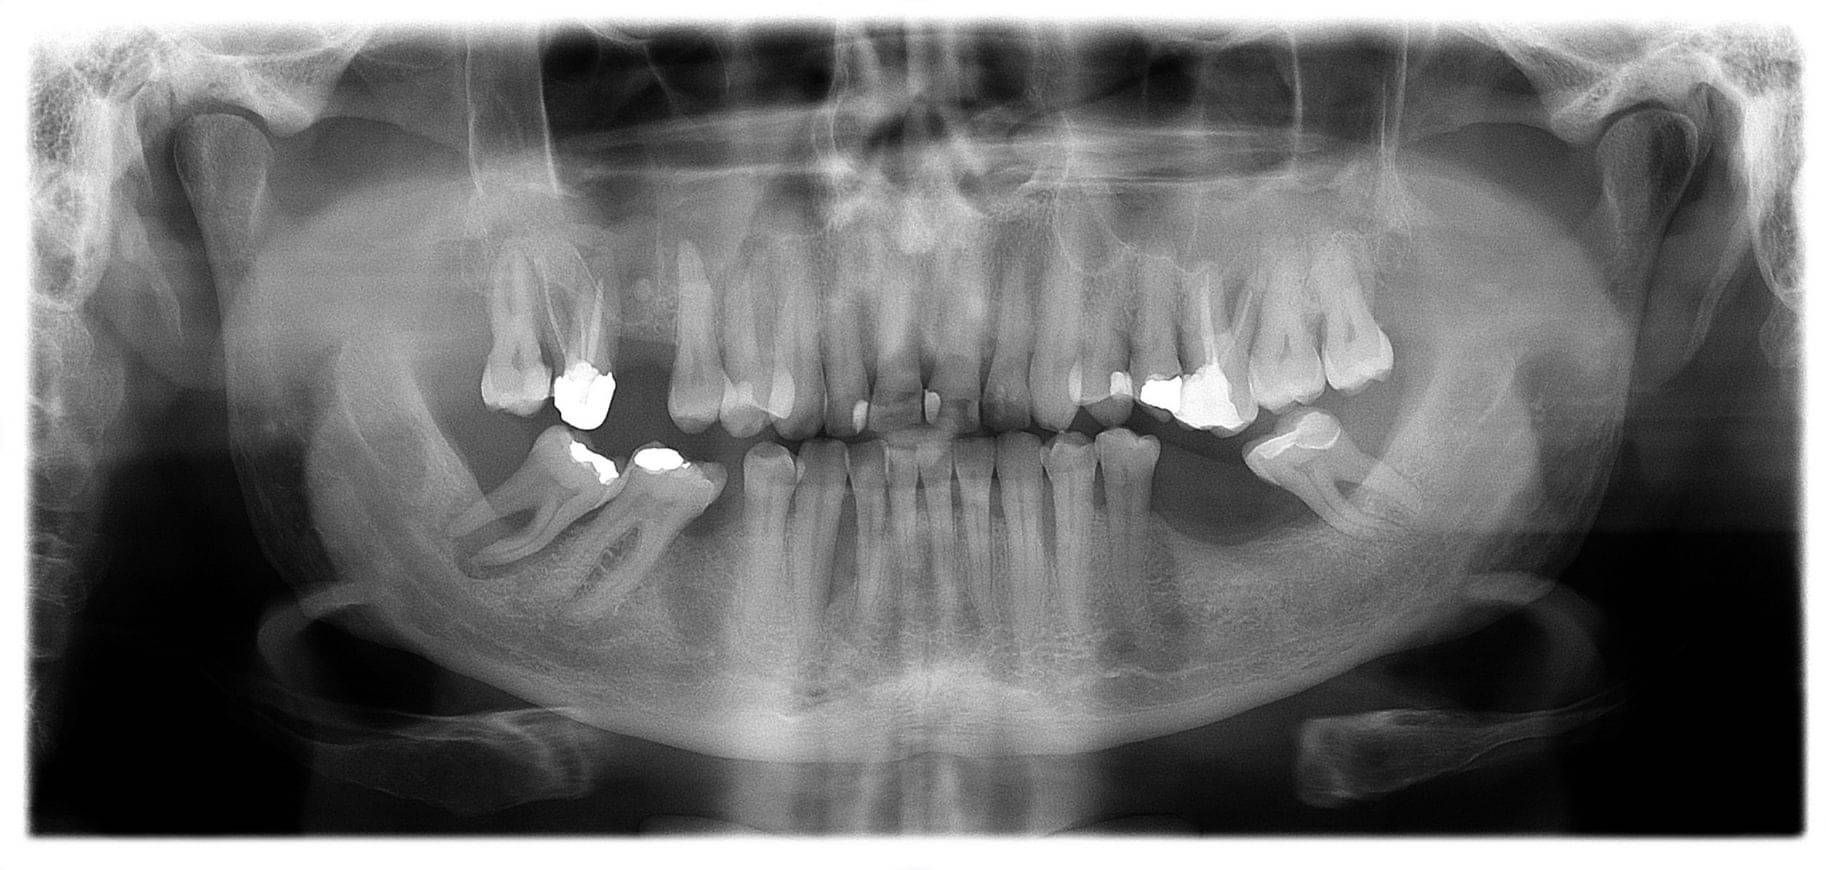

An in-depth oral exam, we will take photographs and examine your mouth, teeth, gums, joint, muscles, tongue and throat and nose. We might check signs of sleep apnoea or reflux, if your history and wear patterns suggest it. We look at saliva and if you have enough; review eating and drinking patterns; medication; oral habits such as clenching or grinding and capture the way you chew in video or with jaw tracking technology. We use AI to evaluate xrays and may request a 3D CT scan of your jaws for complex wear cases and heavily filled mouths.

3D CT Scans: These provide a full view of bone and hidden structures in 3D, important in evaluating very heavily filled mouths and damaged bites.